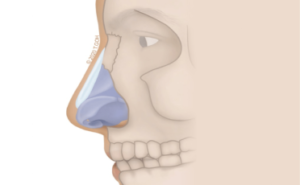

Choosing to combine the intricate skills of microsurgery with aesthetic surgery, Dr Goh specialises in gynaecomastia, surgery of the Asian face, particularly Asian eyelid surgery and rhinoplasty.

Blending the precision of microsurgery with the artistry of aesthetic surgery, Dr Goh has a special interest in gynaecomastia, facial procedures, including ptosis and eyelid surgery, as well as rhinoplasty.